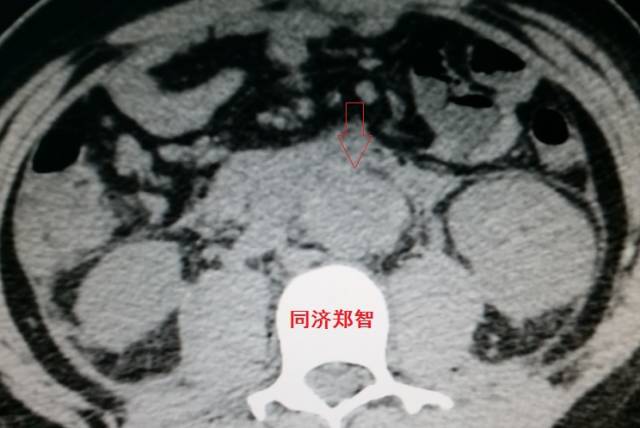

病例十

腹主动脉平扫CT提示正常外周一圈的钙化影中有内移的钙化影(红色箭头所示),CTA 证实为腹主动脉夹层